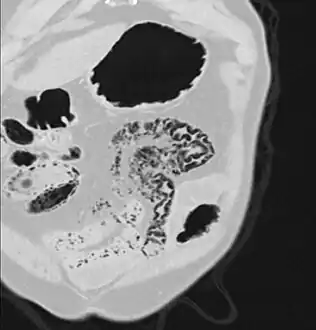

Pneumatosis intestinalis in the coronal computed tomography in lung window. It can be seen next to gas entrapment in the bowel wall and gas in the stomach wall and in numerous vessels, including the portal vein into the liver.

Pneumatosis intestinalis in computed tomography with intestinal ischemia. Lung window for better representation of the gas deposits in the intestinal walls.

Coronal reformatted MDCT image showing extensive pneumatosis intestinalis in the left upper quadrant small bowel. The pneumatosis is more cystic and nodular in the small bowel in the midline and the right of midline. This patient had a relatively benign presentation without bowel ischemia and was treated conservatively.